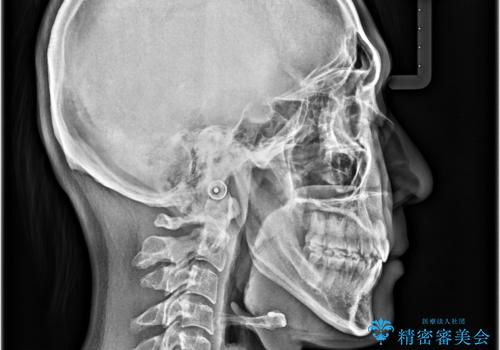

診査の結果、上下顎ともに歯が並ぶスペースが不足しており、上下の前歯が噛み合わない**オープンバイト(開咬)**の状態でした。

歯をすべて並べようとすると口元がさらに前に出てしまうため、上下左右の第一小臼歯を抜歯してスペースを確保し、デコボコと突出感の両方を改善する治療計画を立てました。